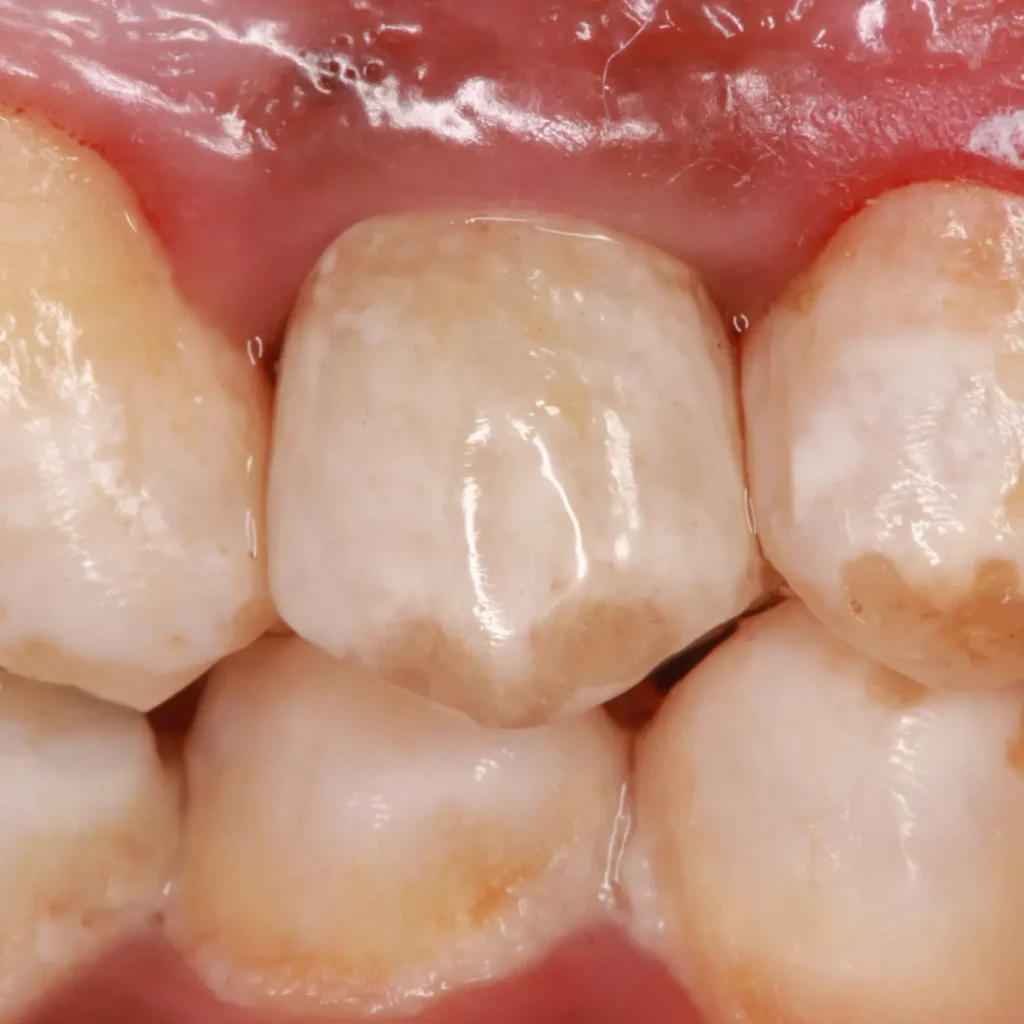

Finally, we made a horizontal prep to receive a zirconium crown with the same characteristics and brown stains that were present in the adjacent teeth.